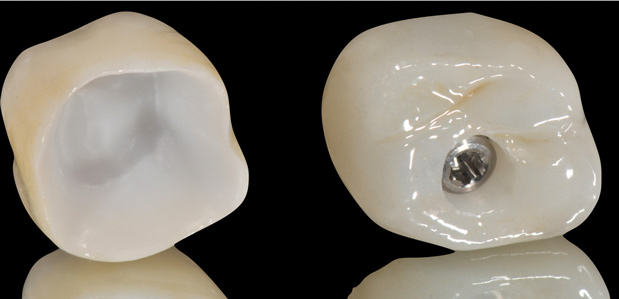

Unfortunately, randomized clinical trials for fully digital workflows for either teeth or implant-supported fixed restorations are scarce. Presently, a strong offering of rapid prototyping procedures exists, including CAD/CAM-produced full-contour or monolithic crowns (Figure 23) and milled frameworks combined with CAD/CAM veneering superstructures. A true digital workflow for crown-and-bridge is not mainstage at present, and barely exists in an analog-digital blend, but the authors believe this will change soon. The layering of porcelain is cumbersome and operator dependent with many working parts and lacks the consistent precision found with today's computerized technology. Joda described a threefold improvement in time efficiency, and either no or minor adjustments of implant-supported crowns, using a digital workflow (intraoral scanning and CAD/CAM technology) in comparison to conventional methods.20 Laboratory time savings have been most impacted by the digital workflow (average 54.5 minutes of production time versus 132.5 minutes), along with a 30% overall treatment cost reduction.21

Fig 23. Full-contour monolithic crowns for teeth and implants constitute the last phase of the digital workflow.

Figure 23